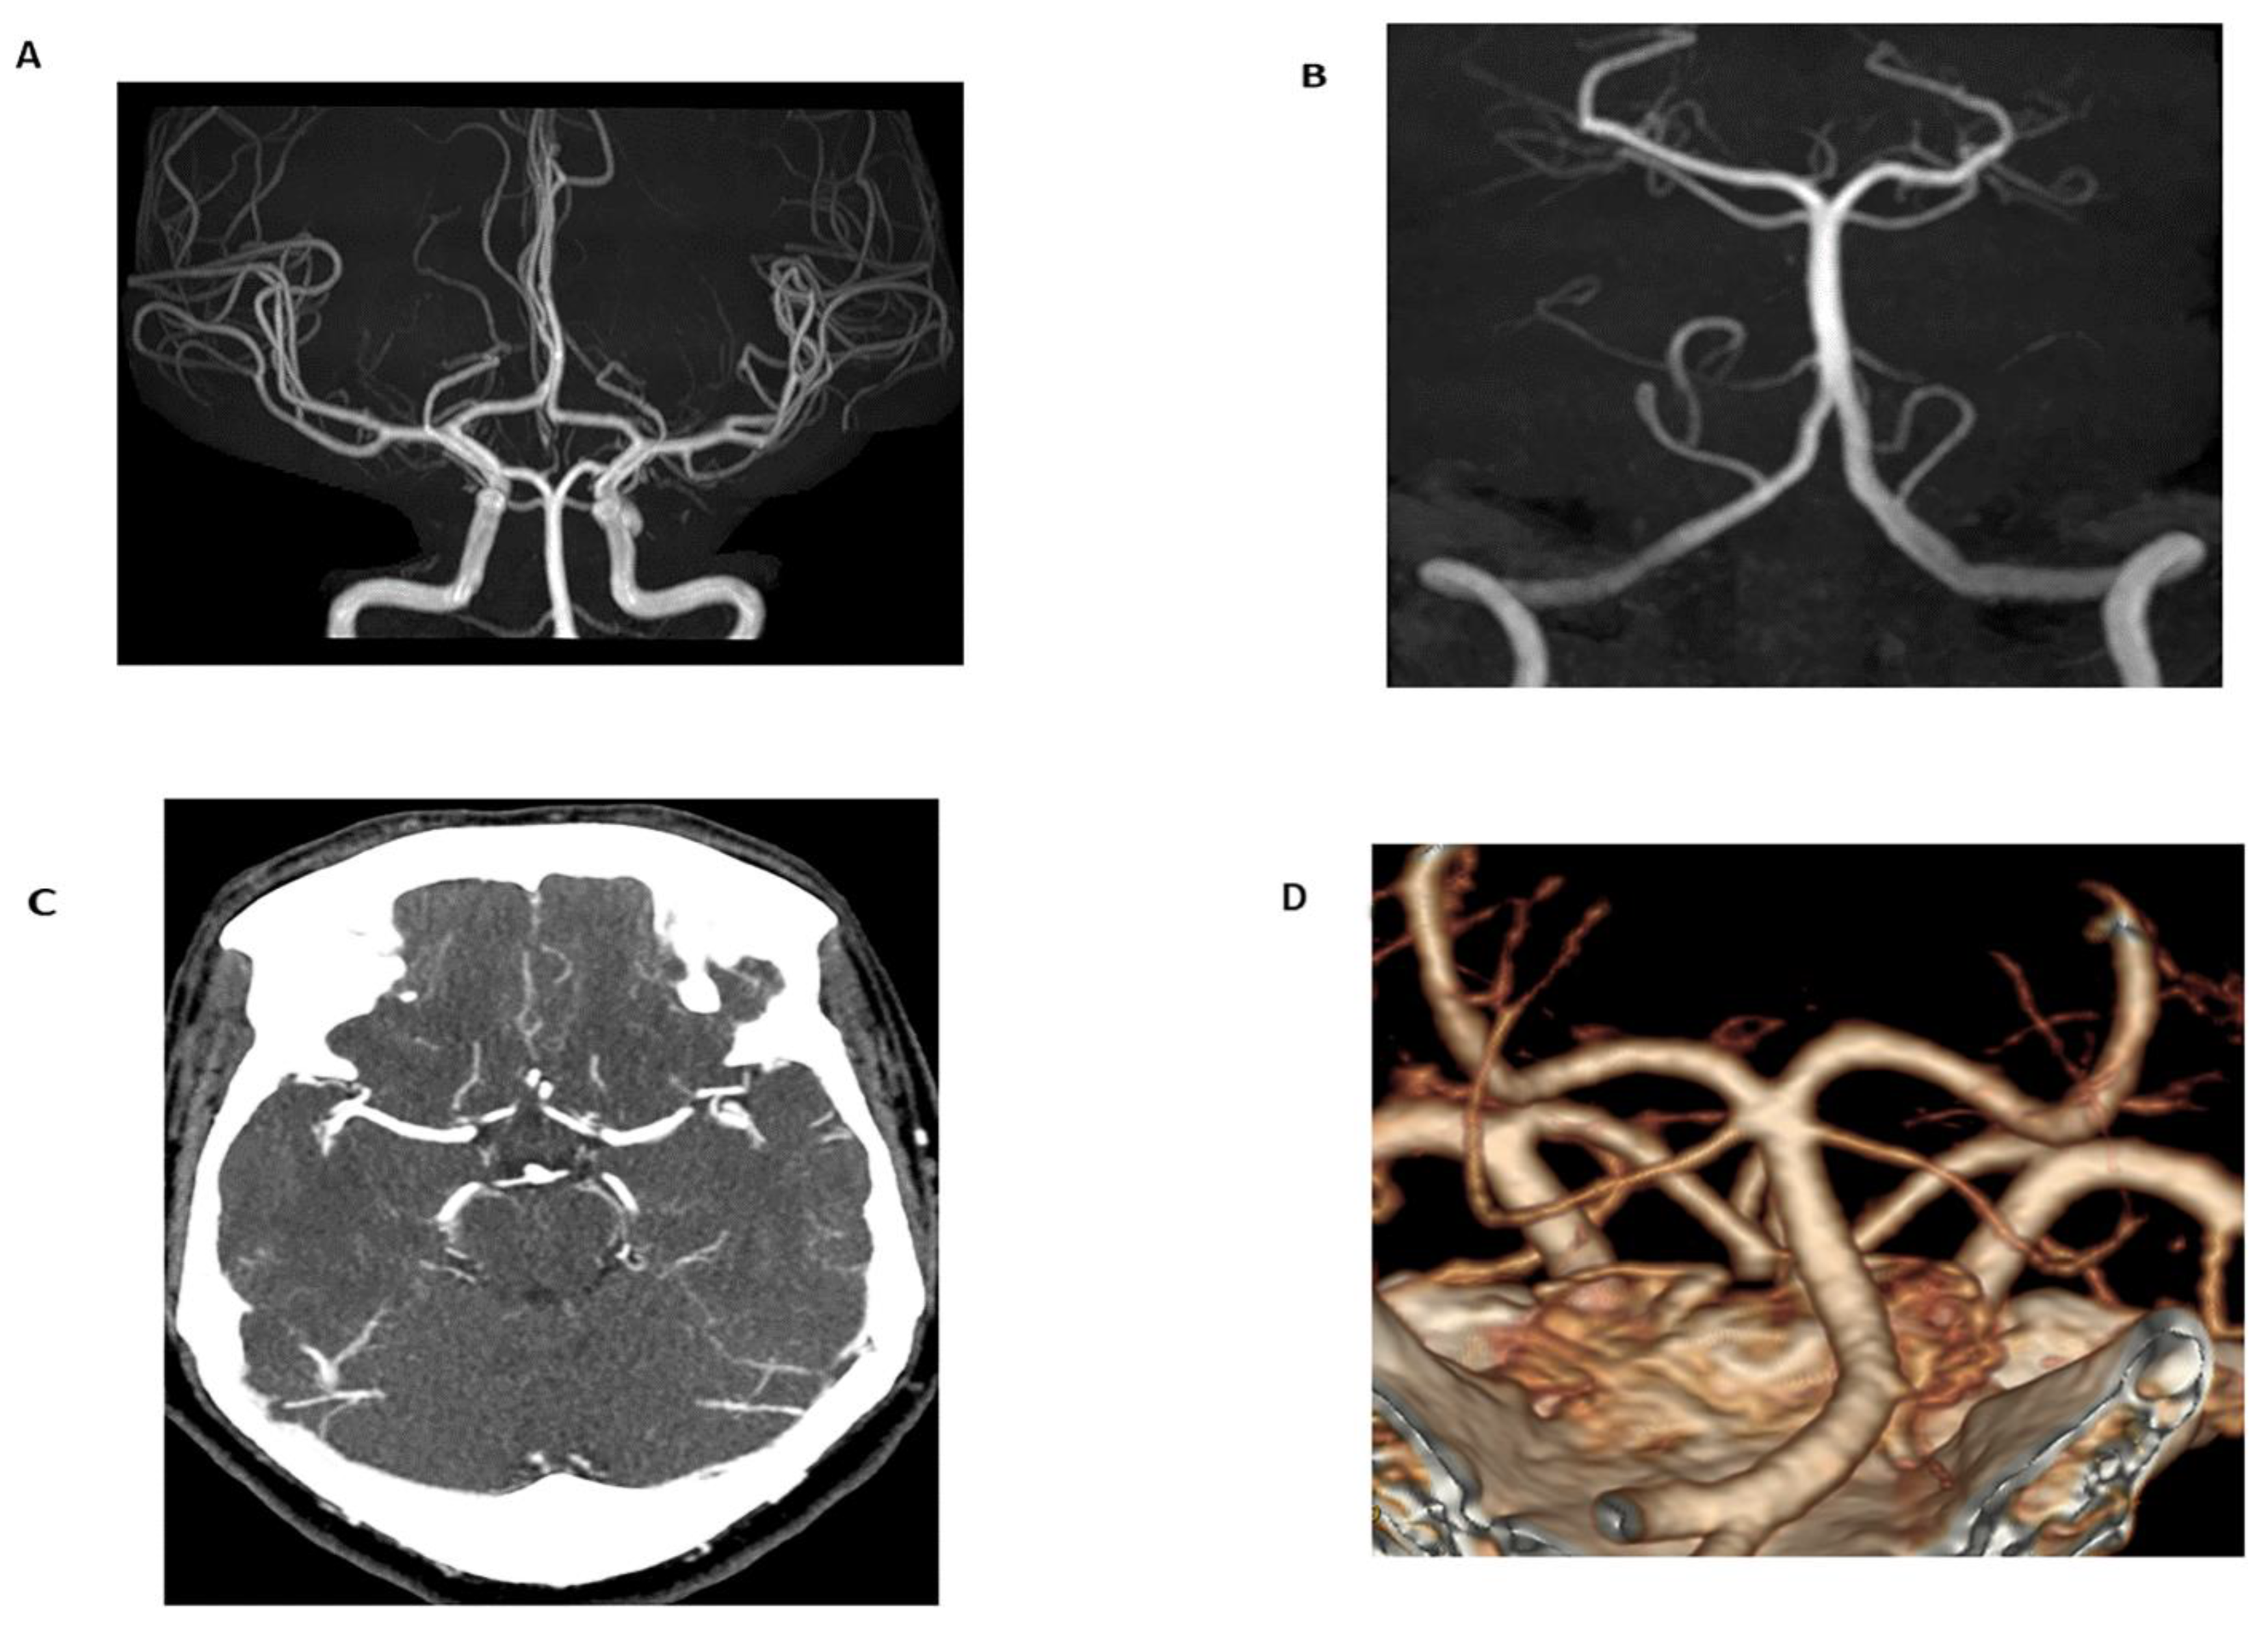

3.2.1. Magnetic Resonance Angiography

- Ren, S.; Wu, W.; Su, C.; Zhu, Q.; Schmidt, M.; Sun, Y.; Forman, C.; Speier, P.; Hong, X.; Lu, S. High-resolution compressed sensing time-of-flight MR angiography outperforms CT angiography for evaluating patients with Moyamoya disease after surgical revascularization. BMC Med. Imaging 2022, 22, 64. [Google Scholar] [CrossRef] [PubMed]